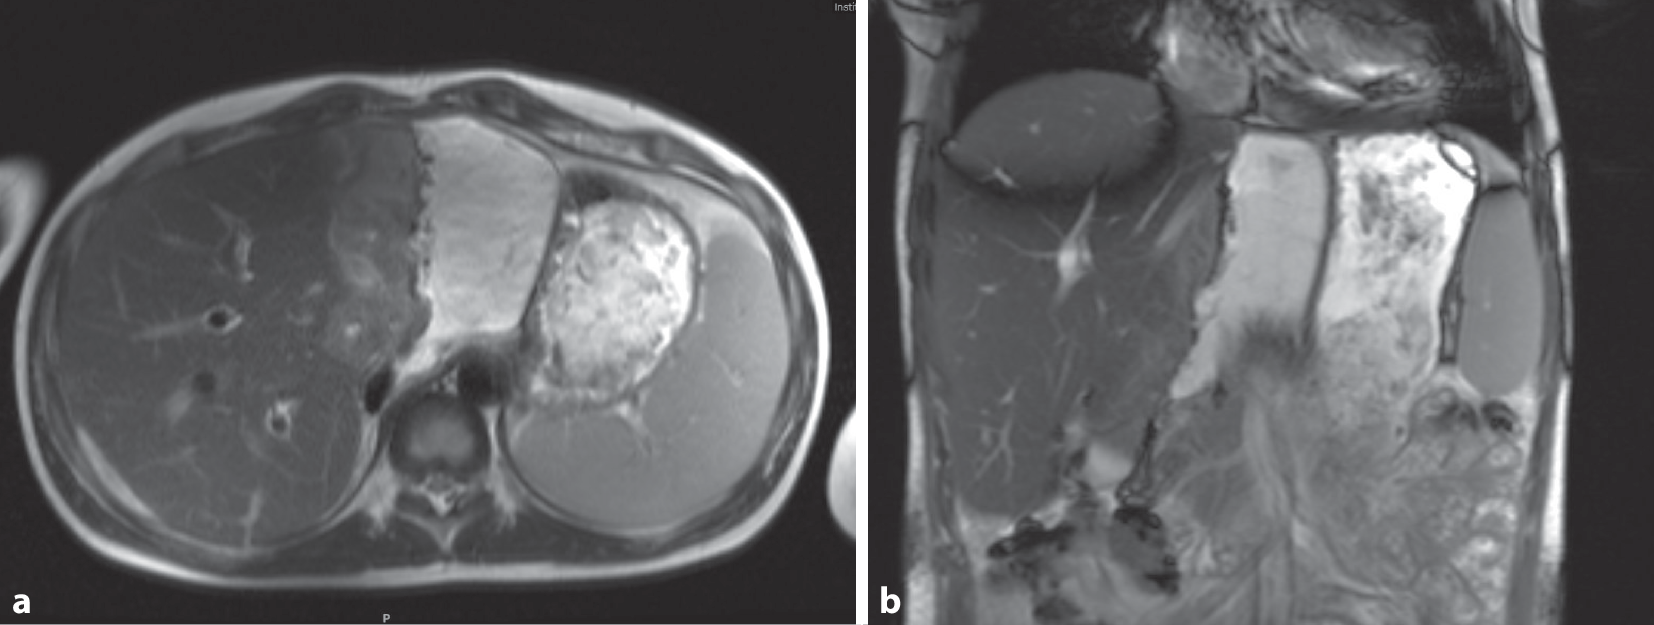

Im weiteren Verlauf kam es zu einem erneuten Anstieg der Entzündungsparameter. In einem daraufhin durchgeführten MRT am 14. postoperativen Tag zeigte sich ein Flüssigkeitsverhalt an der Resektionsfläche, welcher einem infizierten Biliom entsprach (Abb. 5).

Abb. 5

MRT Abdomen mit Biliom. a Biliom im MRT neben der Resektionsfläche, b Biliom in der Coronaransicht